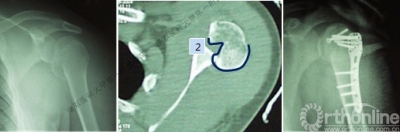

病例1

男性,40岁,摔伤后右肩关节肿痛、活动受限2天。

术后肩关节X线正位片

病例2

男性,48岁,坠落伤致左肩关节肿痛、活动受限1天。

病例1与病例2是同一类损伤吗?

三、影像学

1.X线片

2.肩关节CT

确定肩关节后脱位。

了解反Hill-sachs损伤和程度。

观察肱骨近端主要骨折线和次要骨折线及形态。